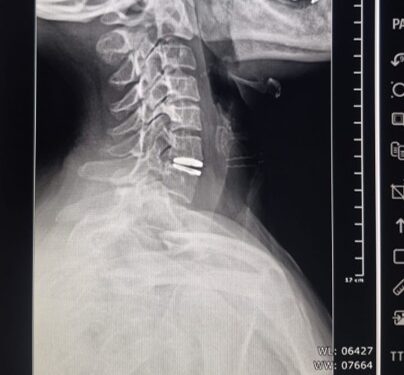

Por primera vez en Villa Mercedes, profesionales del sistema público de salud realizaron un reemplazo de disco cervical con prótesis discal móvil, una cirugía de alta complejidad que preserva la movilidad cervical y evita procedimientos más invasivos. La intervención se concretó el lunes dentro de los nuevos quirófanos del policlínico ‘Juan Domingo Perón’ y constituye un hecho inédito para el sistema sanitario local.

La paciente, una mujer de 48 años oriunda de Fraga, presentaba dolor cervical con irradiación a hombros, con impacto funcional. El procedimiento estuvo a cargo de Sebastián Heredia, médico neurocirujano, junto con el equipo de instrumentación quirúrgica integrado por Virginia Mora e Ivana Altamirano.

Para la colocación de la prótesis discal móvil, participaron técnicos especializados de la ortopedia Zion Corpomedica, contratada por el ministerio de Salud a través de la dirección de Emergencia Sanitaria, dado que la paciente no cuenta con obra social. Todos los costos de la cirugía, la prótesis y la atención fueron asumidos por la cartera provincial.